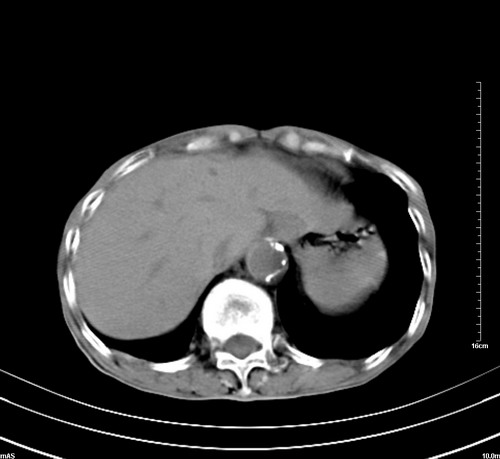

病人,女,79岁,主要因腹疼二月入院,彩超,肝,胆,脾,未见异常,胸透上消化道造影未见异常,化验白细胞增高,内科医生让做胸部ct检查,因为熟人多做了腹部(外科会诊考虑胆囊炎).现ct片如下请假各位战友.

1 气管旁、隆突下淋巴结明显肿大,肝左叶外侧段低密影,都考虑转移。

2 肝右后叶下段明显增大,片状低密影,但因各种伪影显示不佳,不排除病变。

后中纵隔团块影,伴气管、食道受压移位,首先考虑转移瘤,肝s5段低密度灶。建议增强检查,另外其结肠是否有问题请提供,右肺部分肺叶局限含气增多,考虑局限肺气肿。

后中纵隔团块影,伴气管、食道受压移位,首先考虑转移瘤,肝表现同11773。